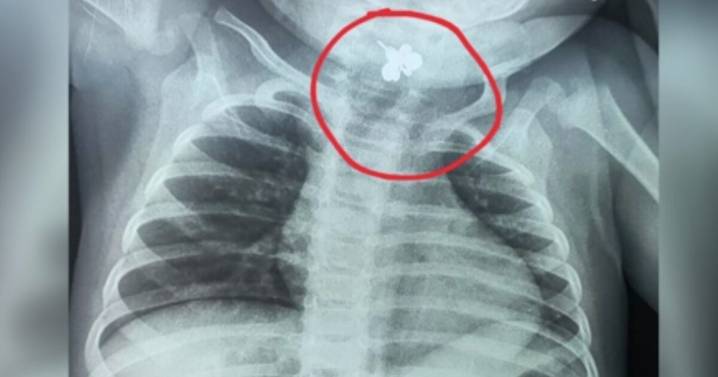

Un caso que encendió las alertas médicas y familiares sucedió en la provincia de Caacupé, donde una bebé de tan solo diez meses aspiró accidentalmente un anillo, situación que fue detectada cinco días después gracias a una radiografía de tórax. Ante la situación, se realizó el procedimiento de extracción, se realizó de manera urgente y concluyó con éxito, evitando un desenlace fatal.

La bebé lactante comenzó a presentar fiebre persistente y dificultad para alimentarse, síntomas que inicialmente fueron tratados como una posible infección urinaria; sin embargo, ante la falta de mejoría y el deterioro del estado general de la menor, los médicos optaron por ampliar los estudios clínicos.

Gracias a una radiografía de tórax, se pudo identificar